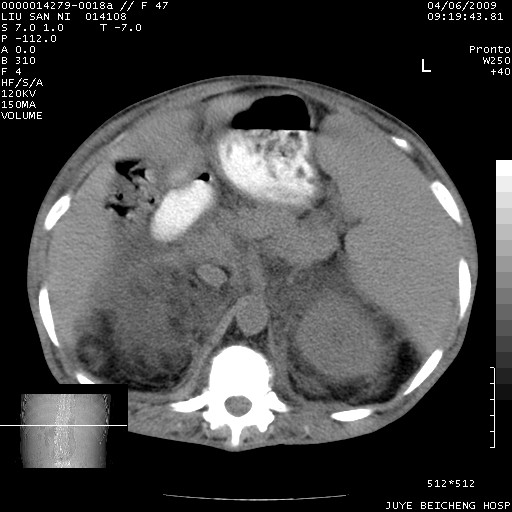

以下是引用前行在2009-4-7 10:31:00的发言:[br]肝脾肿大;双肾增大,双肾盂少量积水可能,肾膜膜增厚,肾周间隙增宽,并见桥间隔,提示结缔组系统疾病、系统性红瘢狼疮肾可能性大。继发右侧胸腔、心包、腹腔积液。

以下是引用深泽交通医院在2009-4-7 11:21:00的发言:[br]双侧肾周密度增高,见条索影,右肾实质见点片状低密度区,考虑弥漫肾炎【自身免疫性?】;;肾性水肿征